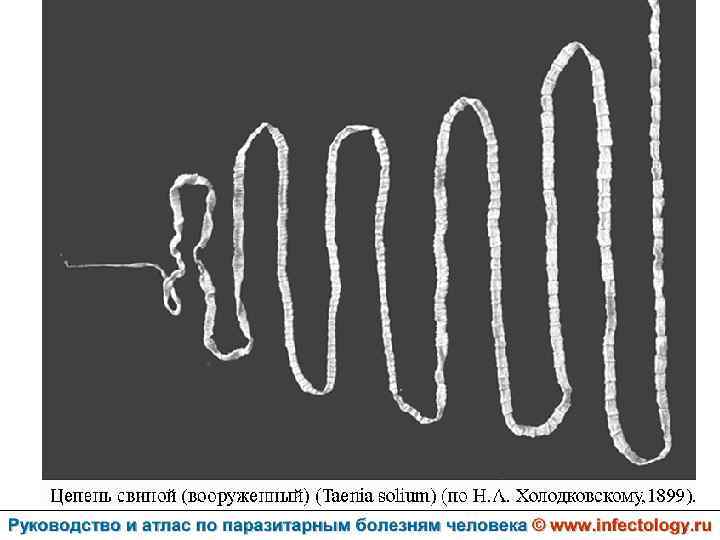

Тениоз (шифр по МКБ 10 - B 68. 0) – антропонозный биогельминтоз, одним из основных клинических проявлений которого является нарушение функций желудочно– кишечного тракта.